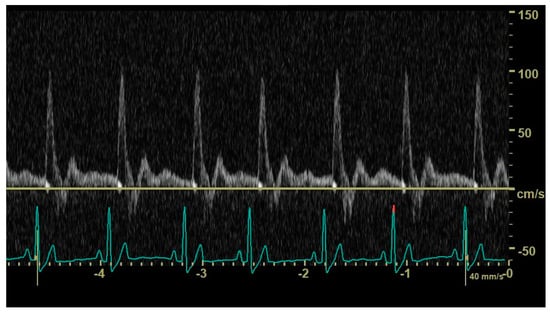

In 12 dogs (4/35 control dogs, 7/37 dogs with an hsPDA and 1/11 dogs with a non-hsPDA), the duration of the diastole did not allow visualization and characterization of the end-diastolic aortic flow (Figure 4). Mean heart rate was 110 (±32) beats per minute in dogs with a visible abdominal aortic end-diastolic flow and 134 (±33) beats per minute in dogs in which this could not be visualized; the difference between mean heart rates was significant (p = 0.024).

Figure 4. Pulsed_wave Doppler ultrasonography of abdominal aortic flow in a healthy dog showing the effect of an increasing heart rate on the end-diastolic flow; in longer cycles, an antegrade end-diastolic flow can be observed, while, in shorter cycles, visualization and characterization of end-diastolic flow are not possible.